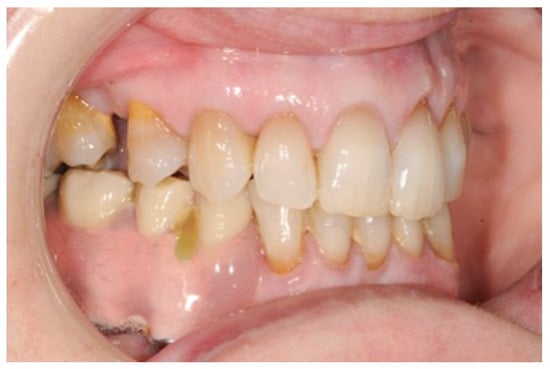

Figure 1.

Clinical case. Orthopantomography (OPT) showing calcifying epithelial odontogenic tumor affecting the right mandible.